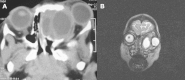

Benign fibrous histiocytoma of the ethmoids in an infant